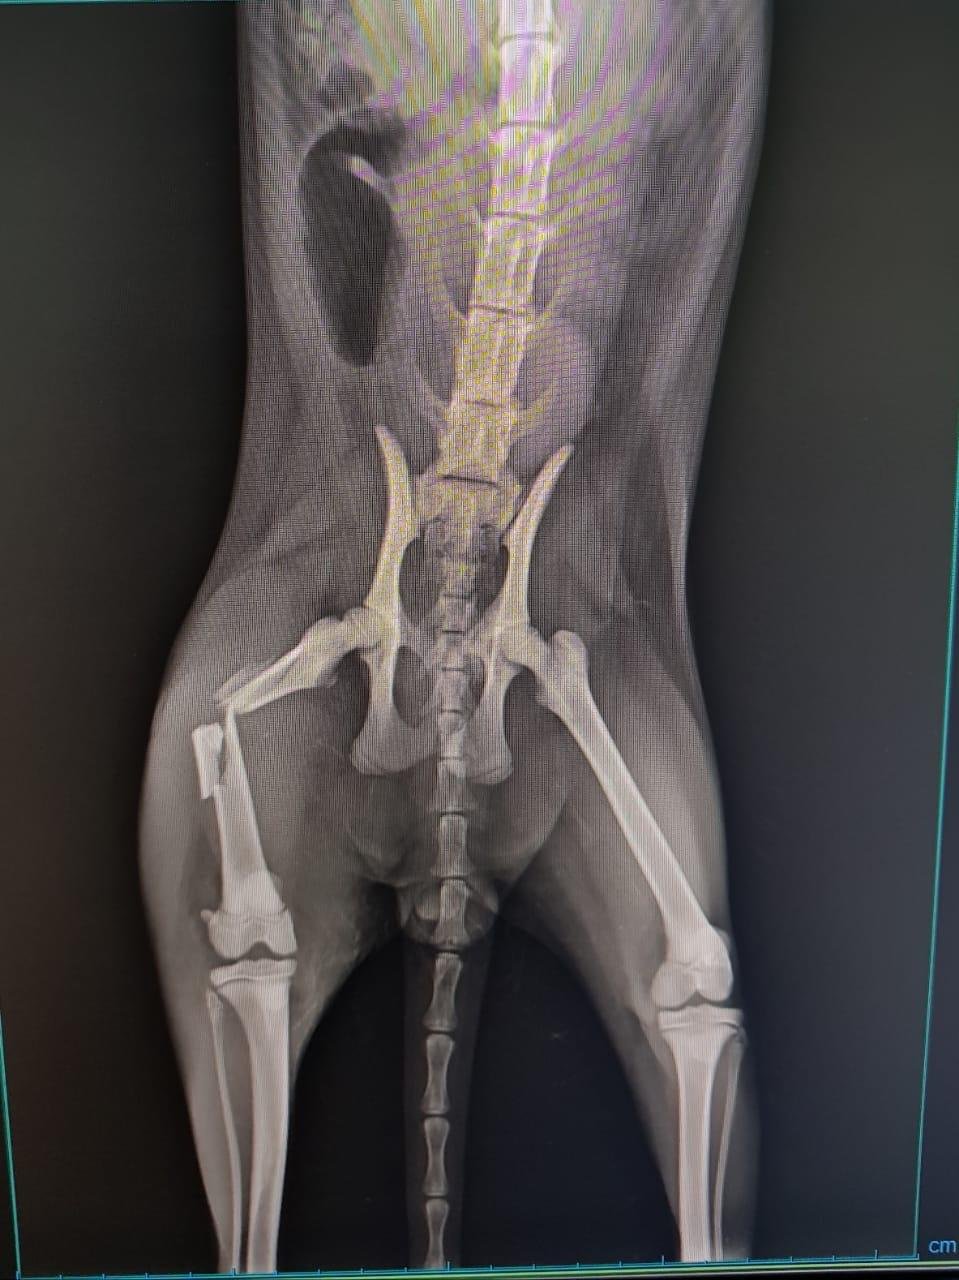

"Olá, Pessoal! Alguns de vocês já me viram pelas redes sociais e alguns já até se disponibilizaram em ajudar, mas eu fui atropelado, atendido de forma emergencial e passei por uma cirurgia bem complicadinha! Fraturei o quadril e quebrei meu fêmur! Mas fui muito forte, bonzinho e valente, além de ser um gatinho muito lindo e especial! Tudo isso custou até o momento R$ 1.440,00, fora medicamentos e outros gastos que poderei ter depois. Estou feliz e agradecido por ter sido socorrido pela minha nova Mamãezinha Lilian, mas contamos com a ajuda de todos que se comoveram com a nossa situação... desde que minha Mamãezinha tem dedicado todo o amor do mundo pra mim, mas não tem condições de pagar essa conta sozinha! Vocês poderiam nos ajudar, por favor? Pode ser com R$ 10 ou a quantia que puderem! Nós agradecemos muito e desejamos de coração que Deus abençoe a todos! Com muita gratidão, Valentin.”